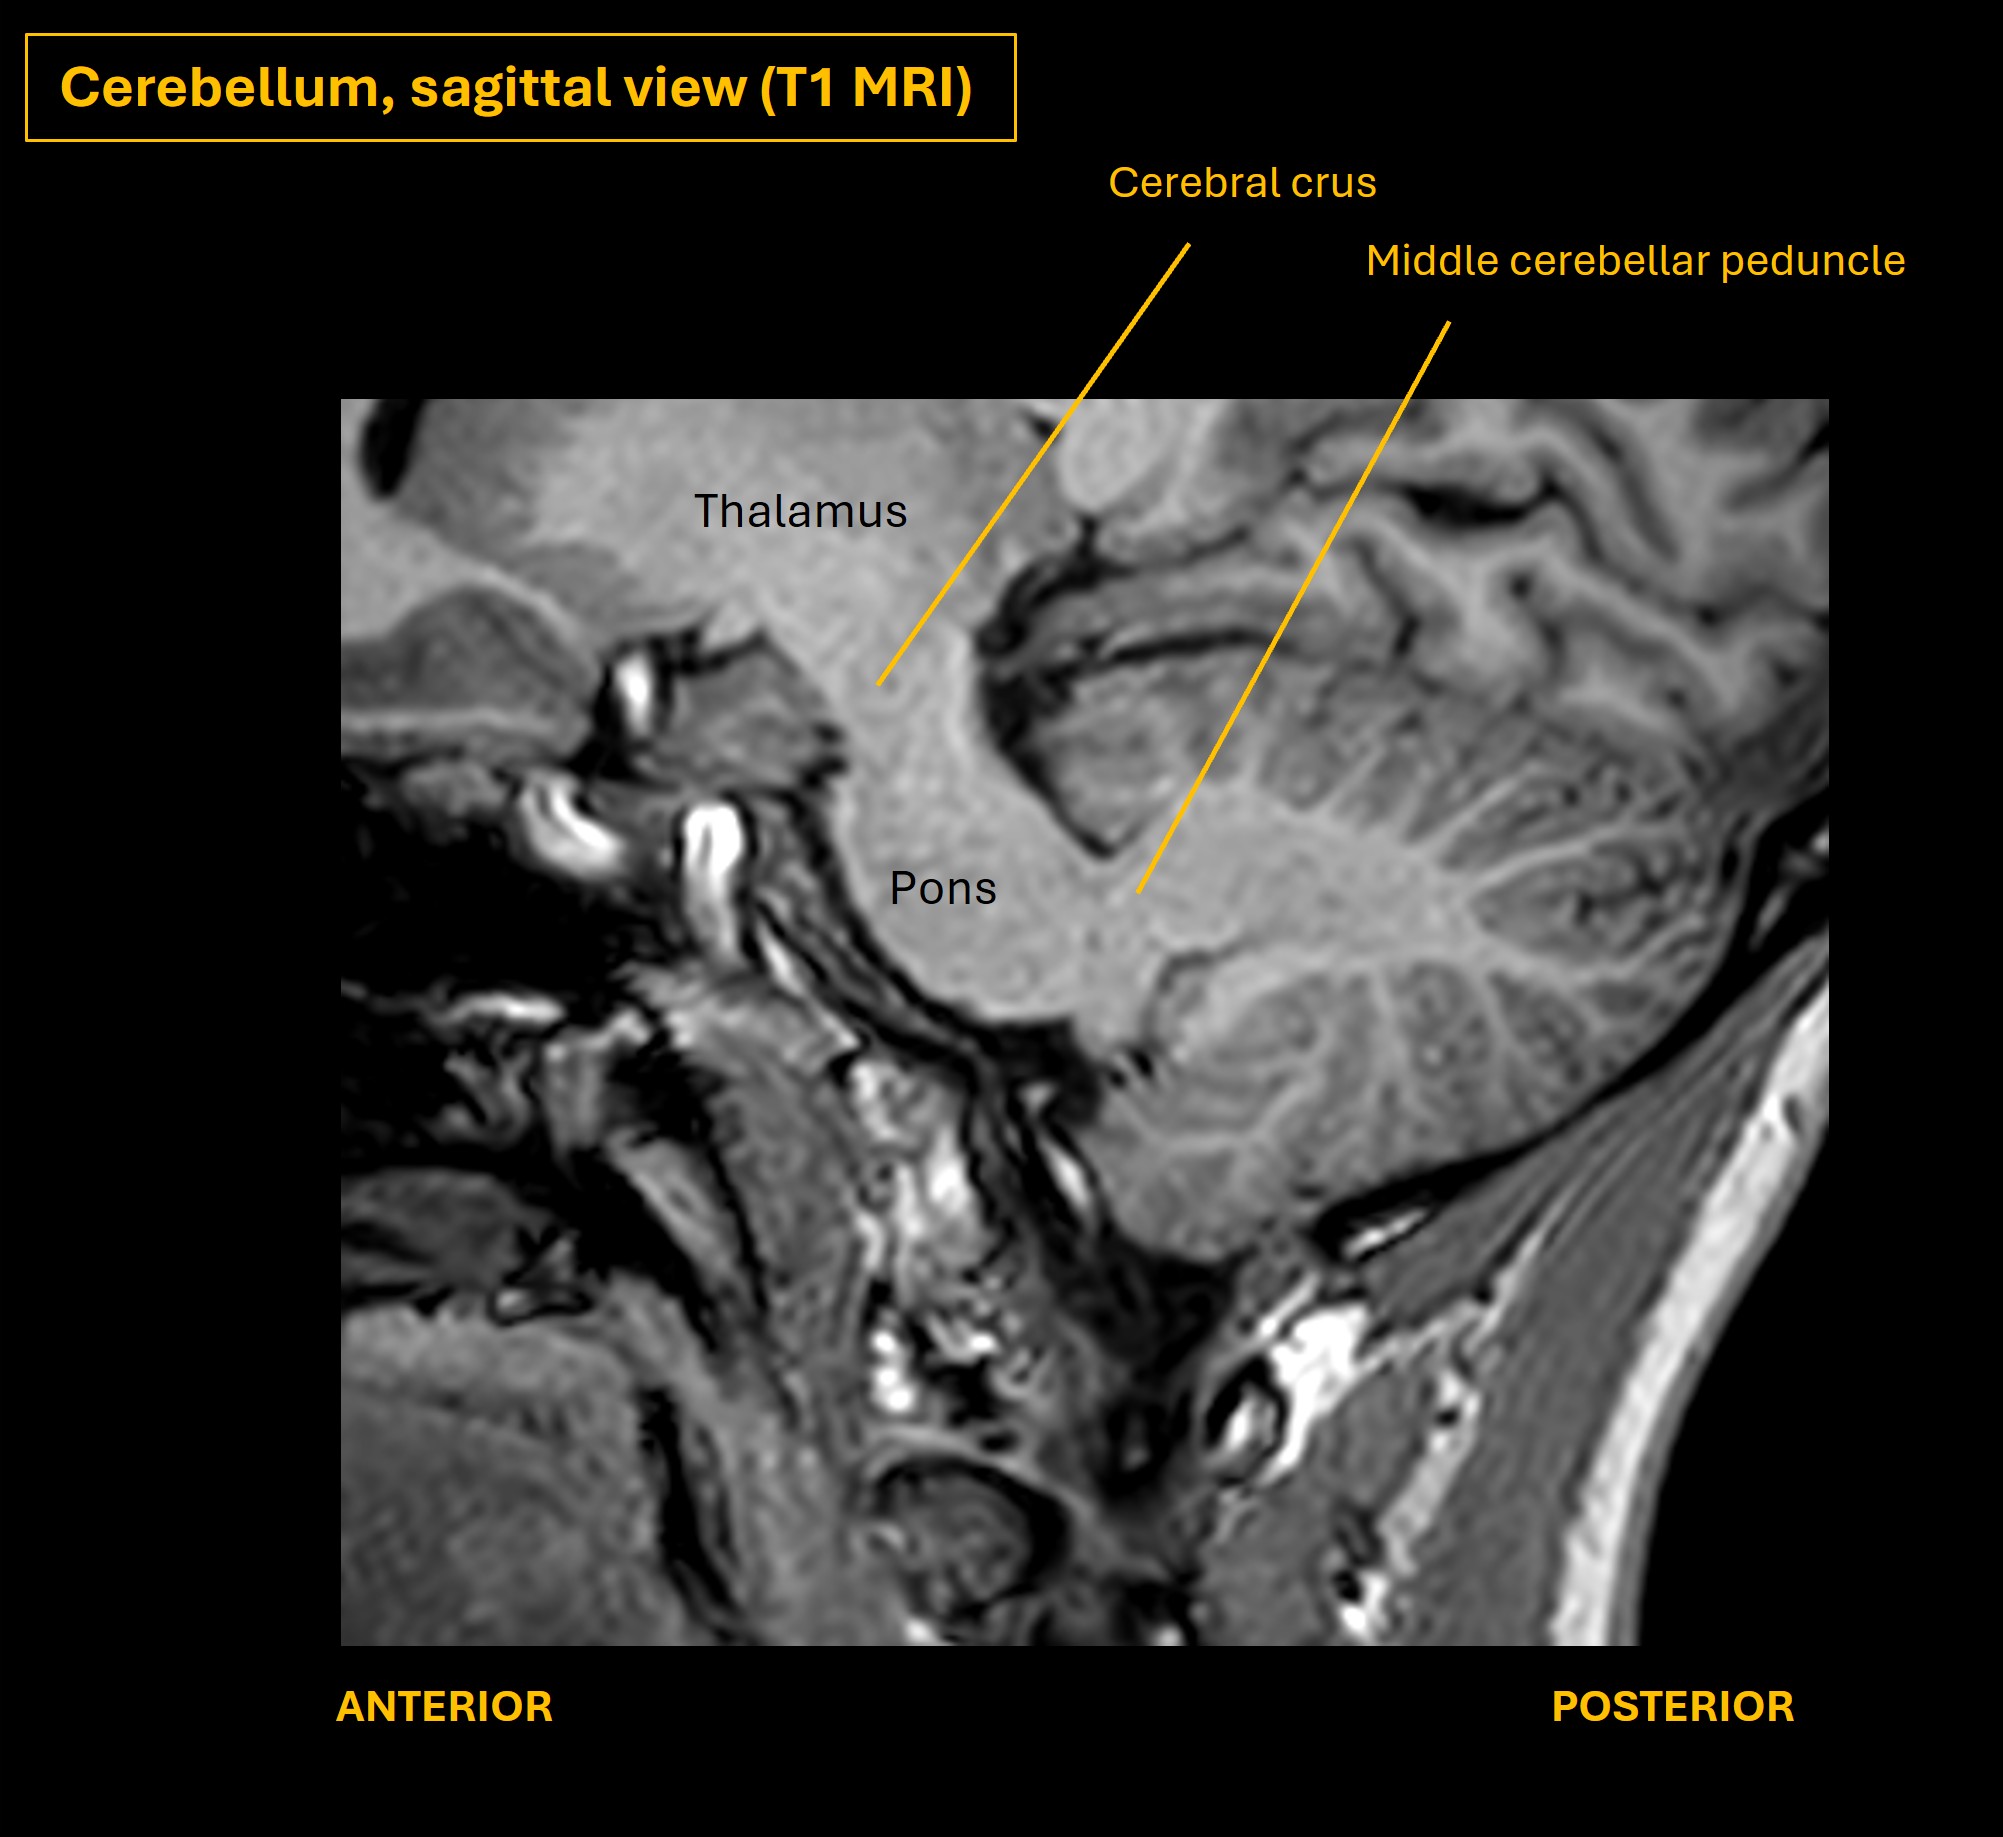

The images below show axial and sagittal views of the cerebellum and illustrate key features and relationships with the brainstem.

The cerebellum connects with the brainstem via the three peduncles - inferior, middle and superior. The middle is very large - forming two broad 'arms' either side of the pons. Many tracts enter and leave the cerebellum through these, involved in control of many functions - posture, balance, gait, targetted limb movements, eye movements and speech.